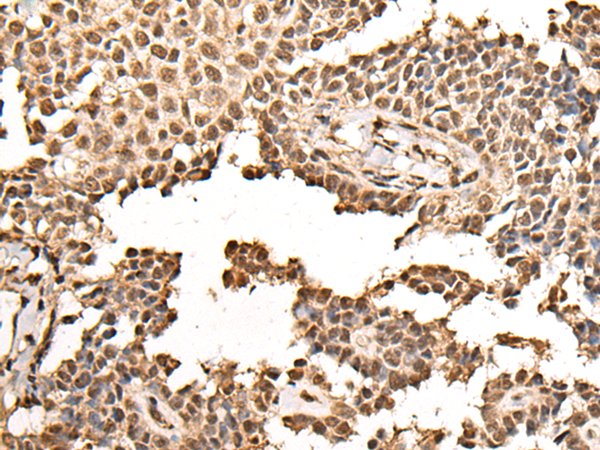

IHC positive control: |

Human ovarian cancer and human thyroid cancer |

IHC Recommend dilution: |

25-100 |